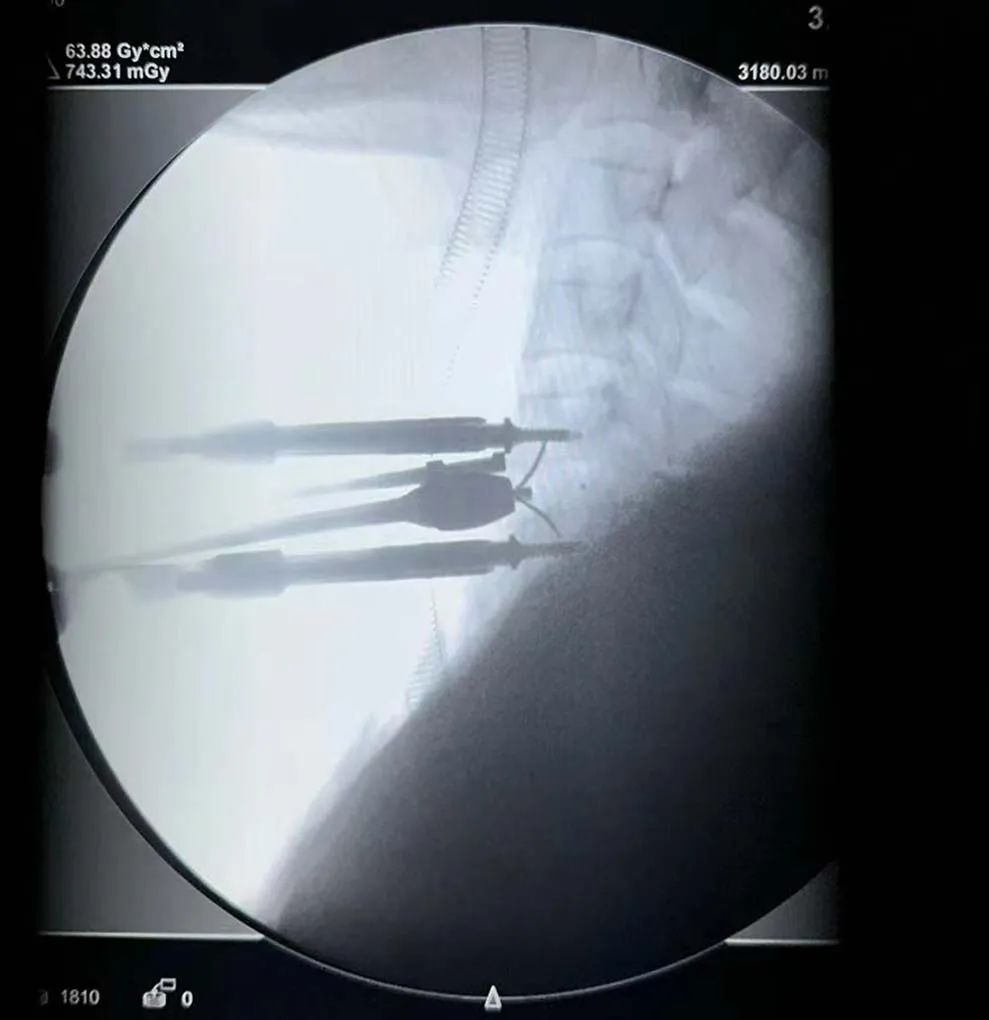

術(shù)中影像

體位透視——

節(jié)段確認(rèn)——